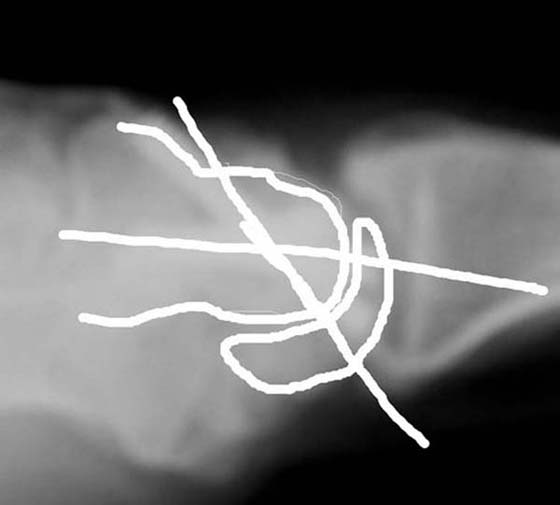

Figure 76-5 B, Four bone fusion lateral X-ray. Note correction of lunate extension to align the central axis of capitate and lunate.

Four-bone intercarpal fusion maintains 50% to 60% of normal wrist motion and 80% of the grip strength on the contralateral side. Long-term studies demonstrate no secondary radiolunate degeneration.6,22

The most common complication after this procedure is dorsal radiocarpal impingement in wrist extension.22,23 This occurs when the lunate is fused in an extended position. The capitate impinges on the dorsal rim of the radius with wrist extension (Fig. 76-6, online). Cohen and Kozin23 proposed fusing the lunate in slight flexion relative to the capitate to avoid this complication and, as a result, provide greater wrist extension.

images

Figure 76-6 Four-bone fusion: lunate fused in an extended position causes capitate impingement on dorsal radius, limiting wrist extension.